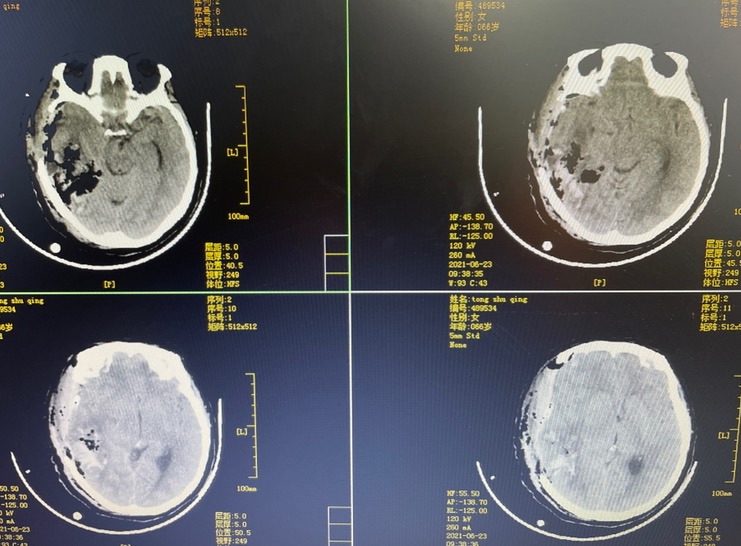

术后一月复查